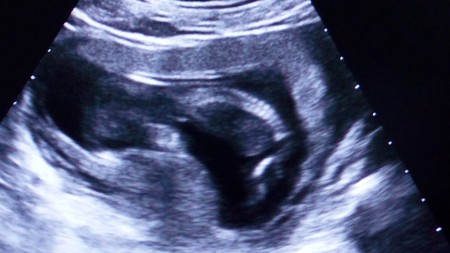

Meraba herkese , Arastırmadaki kendi doktorum cinsiyet söylemedi bir türlü.Bende aynı gün kadın dogum hastanesine gidip bizzat uzman ultrosan doktoruna muayene oldum.detaylı inceledi ve kız dedi ama kesin demiyorum dedi .rüyamda da kız bebek oldugunu gördüm .Resme göre sizin tahminleriniz varmı ? İlerliyen haftalarda pipi gözükürmü bilmiyorum ama kız olmasına cok sevindim inş kız kalır .Allah olmayan herkese nasip etsin .

Gebelik haftası 13 hafta 6 gün